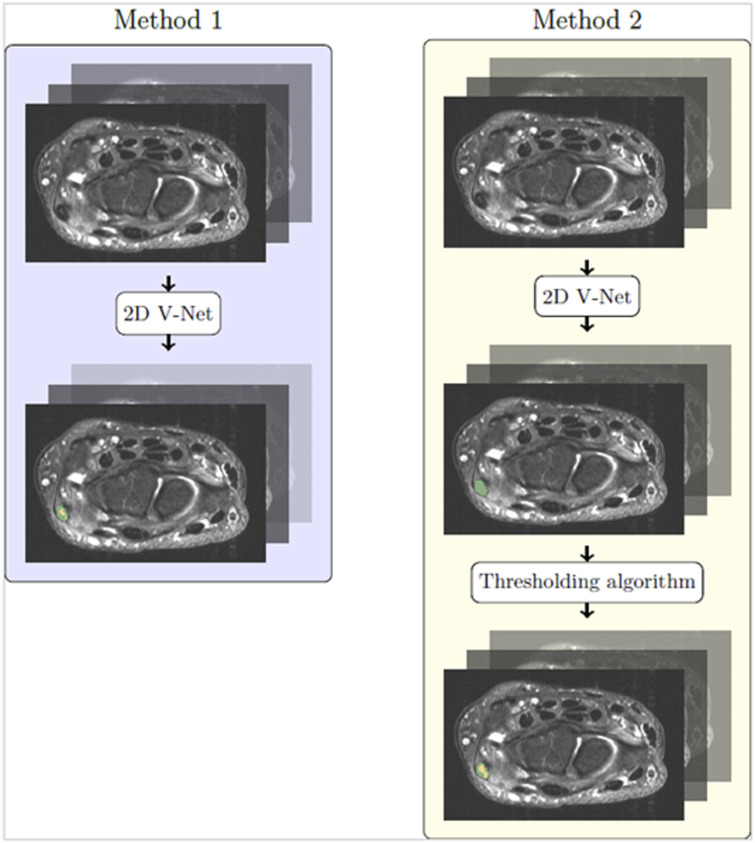

Material and methods: In a retrospective analysis of 1081 patients undergoing wrist MRI imaging, 46 patients exhibited tendinosis. Two deep learning-based methods for segmenting the ECU tendon and T2 hyperintense lesions indicative of tendinosis from 2D axial wrist MRI series were developed and compared in this study. Both methods were trained and evaluated over all 46 patients using Dice score as the main evaluation metric.